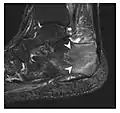

High-energy trauma fractures

Occult osseous injuries may result from a direct blow to the bone by compressive forces of adjacent bones against one another or by traction forces during an avulsion injury. Lesions in the tibial plateau, hip, ankle, and wrist are often missed. In a tibial plateau fracture, any disruption of the posterior and anterior cortical rims of the plateau should be sought. Impaction of subchondral bone will appear as an increased sclerosis of the subchondral bone (Figure 1). In the hip, posterior acetabular fractures also present subtle radiographic findings. The acetabular lines should then be carefully examined keeping in mind that the posterior rim, which is harder to see on X-rays, is more frequently fractured than the anterior rim (Figure 2). In the wrist, detection of carpal bone fractures is often challenging, with up to 18% of scaphoid fractures radiographically occult. Carpal fractures, especially the scaphoid, are associated with the risk of avascular necrosis. In apparently normal wrist radiographs from symptomatic patients, if there is history of a fall on an outstretched hand with pain in the anatomic snuffbox, suggesting scaphoid injury, the initial examination with posteroanterior, lateral, and pronation oblique views must be complemented by other specific views such as supination oblique and the "scaphoid" view A careful examination of cortices for evidence of discontinuity or offset and cancellous bone for lucency is necessary (Figure 3).[1]

Figure 1: A 56-year-old woman presenting with left knee pain after a fall. (a) Initial anteroposterior radiograph was considered normal, however, subtle cortical disruption of the anterior rim of the medial tibial plateau, medial to the tibial spine, is noted (arrow). (b) Coronal T1-weighted MRI confirms the cortical disruption (arrow) and shows extensive fracture through the proximal tibia. (c) Coronal proton density-weighted image with fat saturation shows extensive edema in the subchondral bone. Note also hypersignal adjacent to the medial collateral ligament corresponding to a grade I sprain (arrowheads).[1]